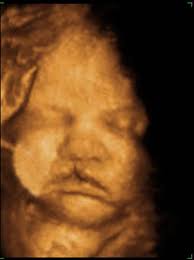

1.) Cleft Lip/Palate

Cleft lip is a gap in the upper lip, which can range in severity and where it is located.

On ultrasound, cleft lip is recognized by a notching in lip. While cleft lip can be isolated (the only abnormality the baby has), it can also be associated with micrognathia (a small jaw), cleft palate (a gap in the roof of the mouth), and a flattened face. Extra amniotic fluid around the baby can also be indicative of a cleft lip, due to the baby having difficulty swallowing properly

Due to these other possible abnormalities being present, we sonographers will pay attention to these other areas to rule out whether the baby has a syndrome (multiple abnormalities present) or if the cleft lip is an isolated finding.